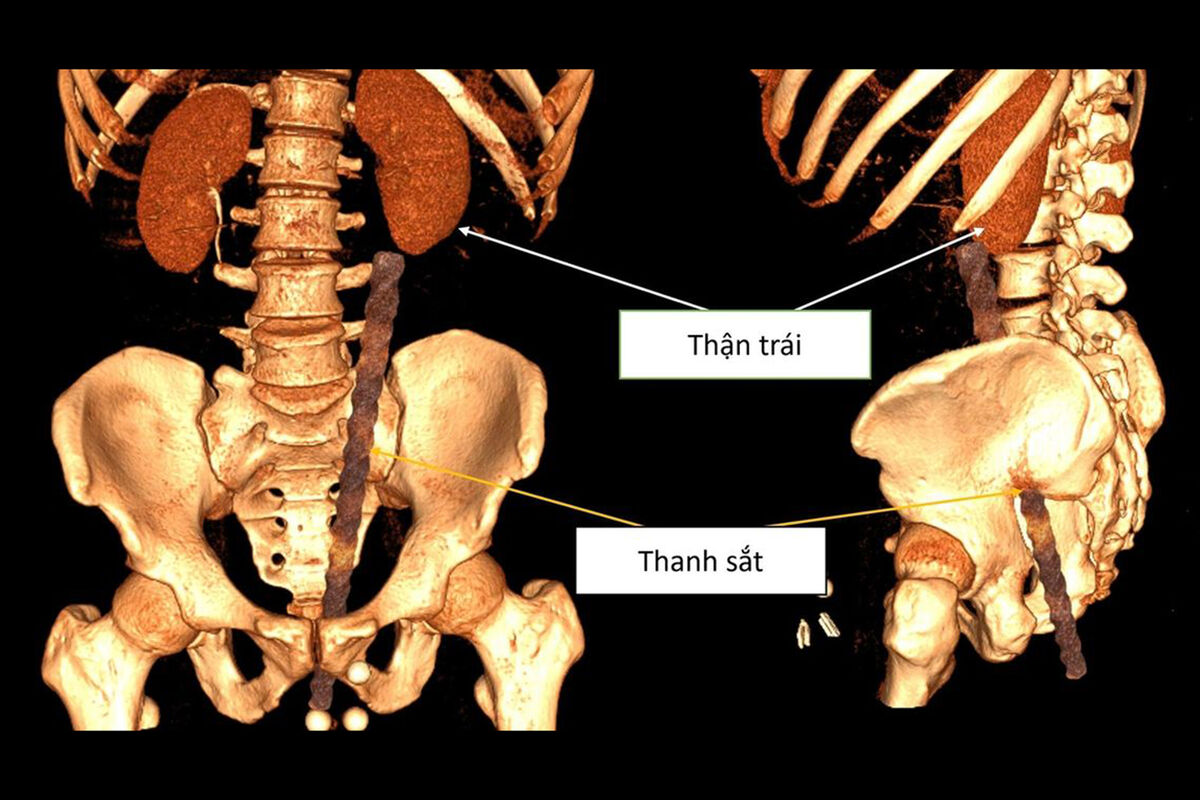

Обследование показало, что арматура вошла через анальное отверстие мужчины и повредила несколько внутренних органов. По данным врачей, металлический прут вызвал сильное кровотечение в анальном канале, мочевом пузыре и брюшной полости. Также были зафиксированы повреждения органов таза.

Во время операции медики обнаружили, что объект находится опасно близко к поясничной области пациента. У мужчины диагностировали ушиб передней стенки прямой кишки длиной около 3 см, повреждение левого мочеточника, разрыв возле почечной лоханки, а также разрыв стенки левой подвздошной артерии, что привело к сильному внутреннему кровотечению и образованию крупной гематомы.